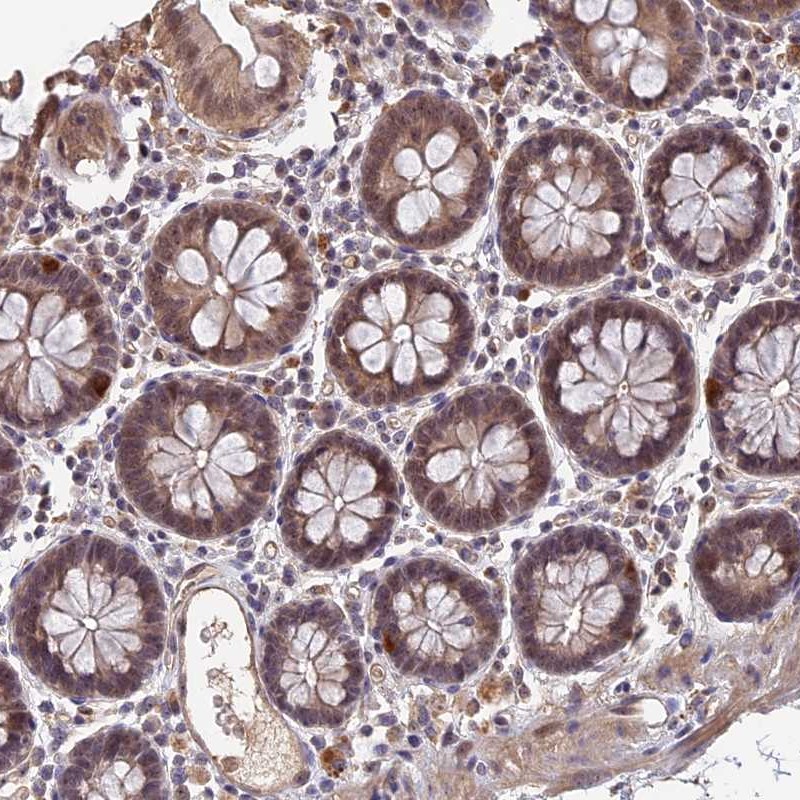

Immunohistochemical staining of human colon shows moderate nuclear positivity in glandular cells.